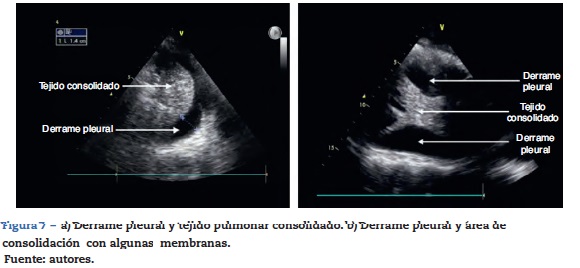

Derrame pleural

El sitio de ubicación de la sonda recomendada es la línea axilar posterior y realizar el barrido ecográfico en diferentes espacios intercostales para determinar el nivel del derrame, luego con la ecografía pulmonar se puede estimar el volumen del derrame y marcar o dirigir el sitio de la punción para su drenaje o estudio. Se debe también estandarizar la posición del paciente en el momento de hacer la medición y suele ser entre 0 y 15 grados de inclinación21. Como se mencionó previamente, el derrame pleural está conformado en su gran mayoría por una fase líquida la cual podemos evidenciar en la US como un área anecoica (fig. 7), es importante identificar esta colección en la parte de arriba del diafragma, y se recomienda valorar otros signos semiológicos para poder determinar realmente la presencia de líquido en el espacio pleural20,28,31. Se buscará en modo M, y es el signo «sinusoidal» en el que el área anecoica cambiará su dimensión con el ciclo respiratorio.

Esta información obtenida por ultrasonido puede también ayudar a sospechar el tipo de líquido presente en las pleuras. Es probable encontrar en derrames grandes áreas de consolidación o probablemente atelectasias por compresión del tejido pulmonar, también en algunos casos se pueden encontrar imágenes como membranas o segmentos irregulares móviles que se conocen como el signo del «plancton» el cual esta más relacionado con hemotórax o empiemas. Algunas imágenes pueden aparecer con tabiques o septos también correlacionados con estas mismas entidades.

Así pues, esta herramienta ofrece una ayuda diagnóstica temprana en la diferenciación del tipo de colección que puede estar en un derrame32.

Dentro de los hallazgos que se debe encontrar por ultrasonido, es la similitud del tejido pulmonar consolidado a el tejido de órgano sólido (fig. 7), por lo tanto es necesario hacer una evaluación juiciosa de los diferentes sectores de los campos pulmonares28,31.